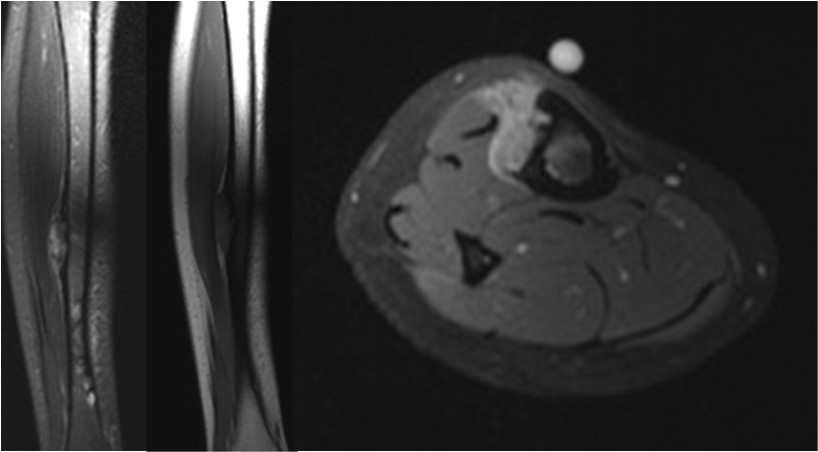

Bei ihr wurde im Herbst 11 ein bösartiger Knochentumor im linken Schienbein entdeckt Die anschliessende Chemotherapie griff ihr Herz so stark an, dass man Carina im September 12 an ein. Endgültig zeigt ein Röntgenbild die typischen Veränderungen durch einen Knochentumor Bestehen Zweifel, ob es sich um gut oder bösartige Tumoren handelt, sind zusätzliche Untersuchungen notwendig, zum Beispiel eine Computertomographie ( CT ) oder eine Magnetresonanztomographie ( MRT ). An artificial knee joint has one part of a femur for attaching to the distal part of a femur and a tibia part for attaching to the proximal part of a tibia The femur is made of aluminium oxide, aluminium dioxide ceramic, zirconium oxide or zirconium dioxide ceramic;.

Gutartige Knochentumoren unterscheiden sich in Ätiologie, Pathogenese und Pathophysiologie Angesichts der zeitlichen Assoziation zum physiologischen Knochenwachstum ist anzunehmen, dass ihr Wachstum durch die gleichen Prozesse mit beeinflusst wird Die meisten benignen Knochentumoren treten sporadisch auf, einige wenige auf dem Boden genetisch bedingter Prädispositionen (z B hereditäre. Ein Knochentumor ist eine Gewebemasse, die sich formt, wenn sich die knochenbildenden Zellen unkontrolliert teilen Eine wachsende Masse kann das gesunde Gewebe durch ein abnormes schwächeres Gewebe ersetzen Der Knochentumor kann verursachen einen Bruch der Knochenbälkchen (Trabekel), aus denen das Knocheninnere besteht, eine Fraktur. Endgültig zeigt ein Röntgenbild die typischen Veränderungen durch einen Knochentumor Bestehen Zweifel, ob es sich um gut oder bösartige Tumoren handelt, sind zusätzliche Untersuchungen notwendig, zum Beispiel eine Computertomographie ( CT ) oder eine Magnetresonanztomographie ( MRT ).